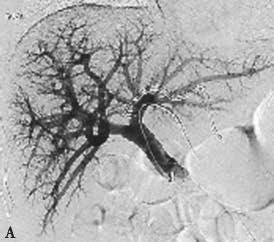

PVE栓塞材料多样,包括弹簧微钢圈、明胶微球、吸收性明胶海绵、凝血酶、超乳化碘油、纤维蛋白胶、无水乙醇、聚乙烯醇颗粒、氰基丙烯酸正丁酯(N-Butyl cyanoacrylate,NBCA)等,多种材料个体化联合应用能够增强栓塞效果(图2-5-1)。

图2-5-1 采用不同栓塞材料实施PVE

A、a.弹簧微钢圈栓塞门静脉右支;

B、b.氰基丙烯酸正丁酯栓塞门静脉右支和Ⅳ段支;

C、c.微钢圈联合氰基丙烯酸正丁酯栓塞门静脉右支。